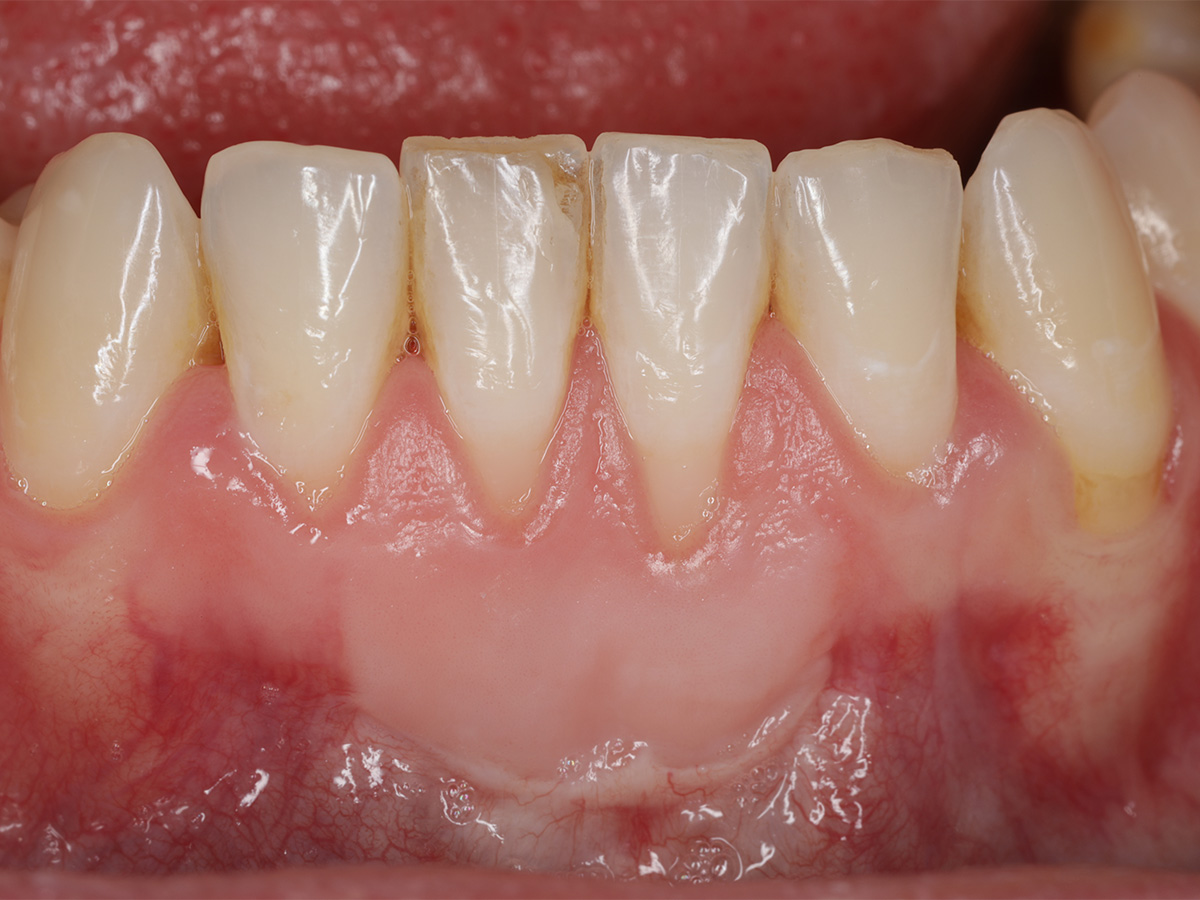

Abbildung 5

Klinische Situation 13 Monate nach Weichgewebsaugmentation.